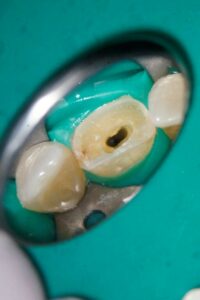

Guttapercha und AH Plus als Sealer. Anschließend wurden aufgrund der ovalen Kavität zwei Glasfaserstifte zur Stabilisation der Füllung eingebracht und mit Luxacore adhäsiv verklebt.

Der provisorische Aufbau erfolgte durch den Endodontologen mit vorab gefertigtem Silikonschlüssel mittels Tetric Flow und Ceram A3,5 als Abschluss der Single-Visit-Behandlung. Die endgültige Krone konnte am 12. Juni 2025 eingegliedert werden.